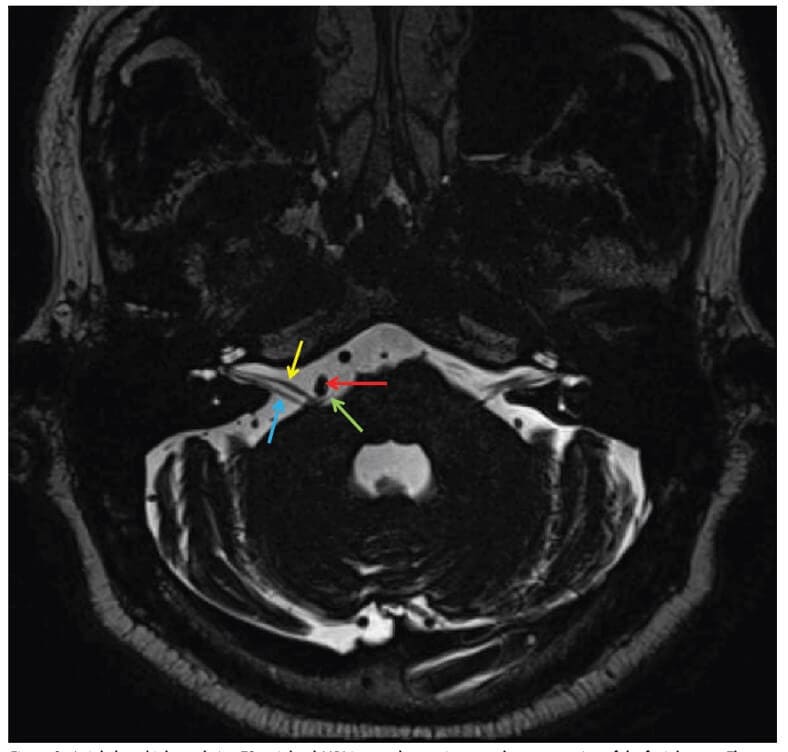

Upon examination, the patient’s Snellen distance visual acuity is 20/20 OD and 20/20 OS. Pupils, EOMs, confrontation visual fields do not show signs of pathology. Color vision is full OD/OS. Hertel exophthalmometry, MRD1 and levator function are symmetric between the two eyes. No pathology was noted in the anterior segment and posterior segment of either eye. On external observation, there is an obvious, constant spasm of the right lower lid, the right upper lid, and the right upper cheek corresponding to the zygomatic muscle. The remainder of cranial nerve testing: CN V, VIII-XII is intact. Right sided upper and lower eyelid spasm with additional involvement of the right zygomatic muscle prompts an MRI of the brain with and without contrast to assess the root and the course of the right facial nerve with attention to the pons/cerebellopontine angle. MRI imaging interpreted by the radiology team detects the right vertebral artery and the right anterior inferior cerebellar artery branch displacing the right seventh cranial nerve at the root exit zone, confirming a diagnosis of primary hemifacial spasm due to microvascular compression.

Figure 1: Axial-plane high resolution T2-weighted MRI image shows microvascular compression of the facial nerve. The yellow arrow shows R CNVII, the blue arrow shows R CNVIII, the red arrow shows R vertebral artery and the green shows the anterior inferior cerebellar artery branch.